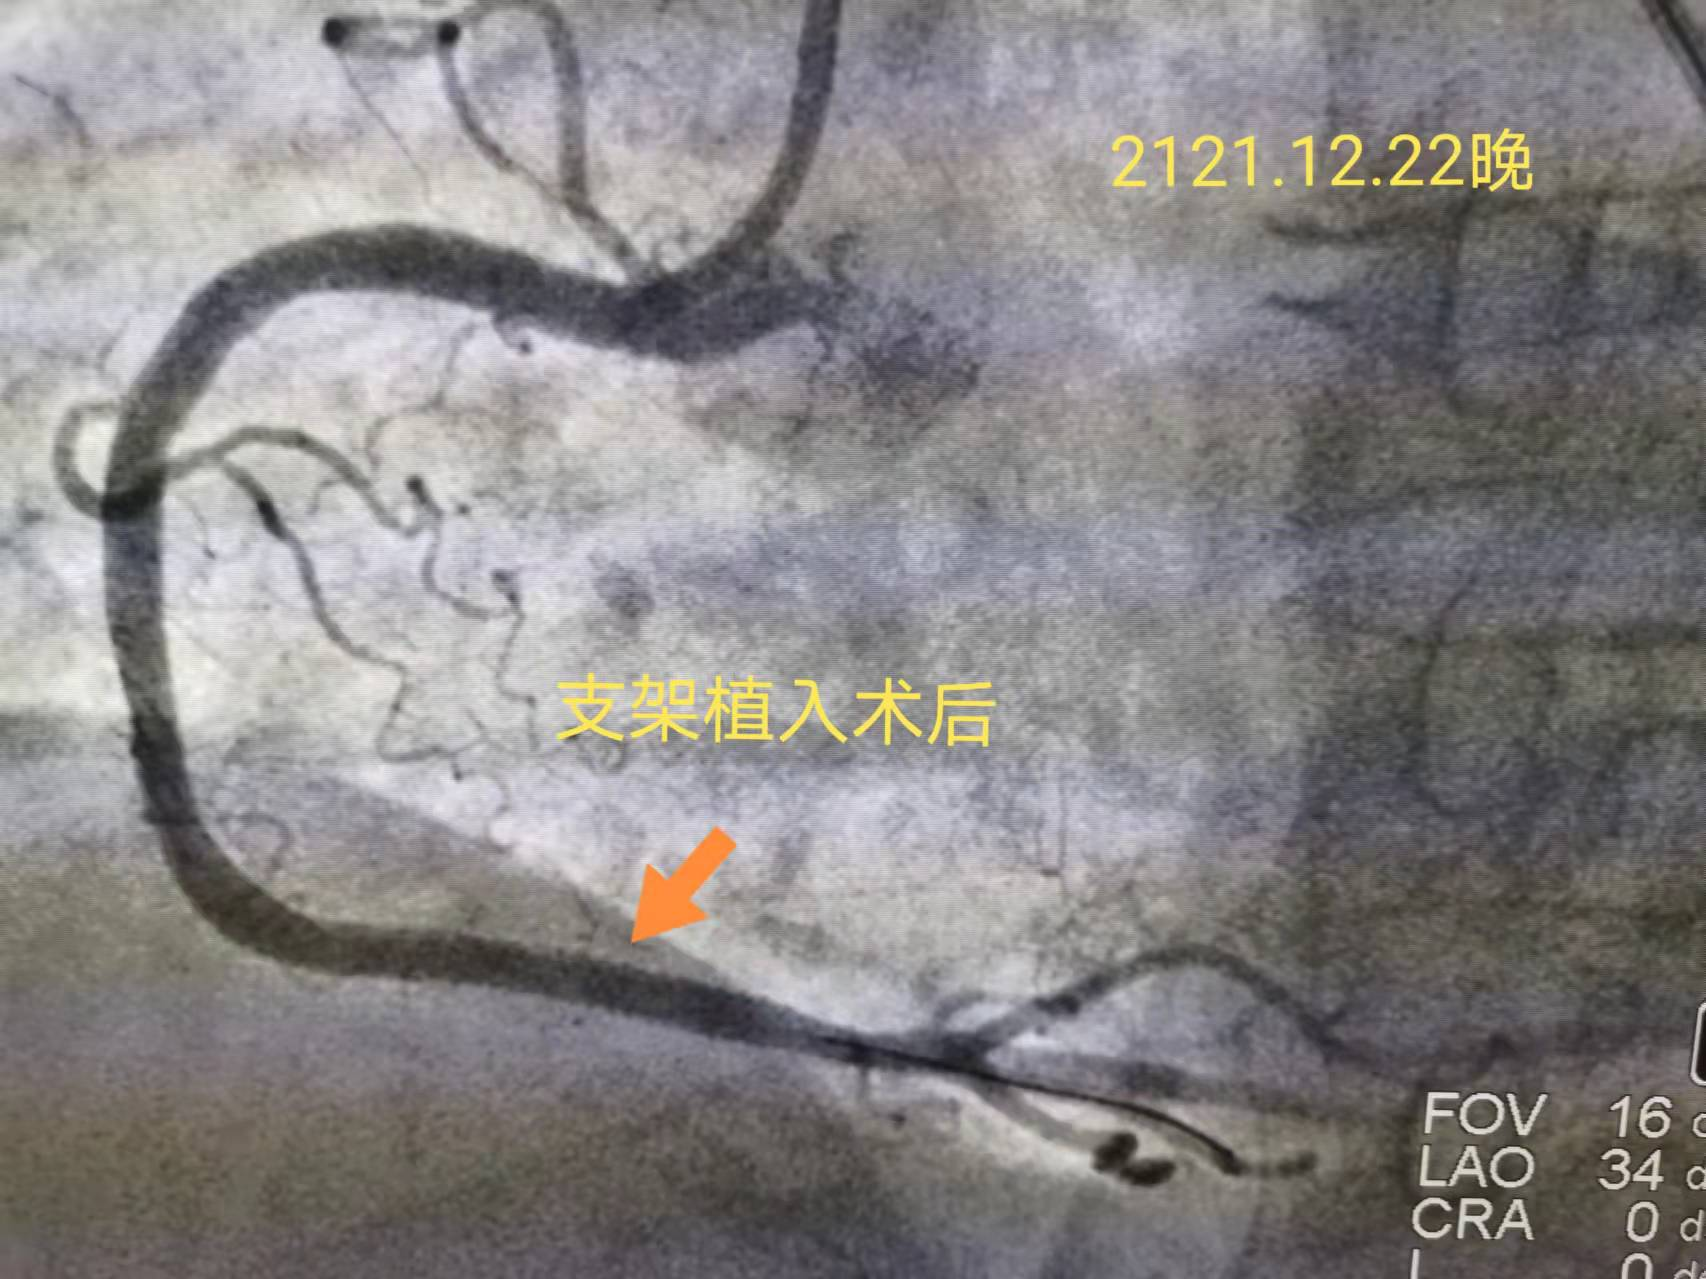

23时50分,急诊PCI手术开始了。邹医生按照急性心肌梗死救治流程,快速完成冠状动脉造影,通过导丝行球囊扩张及支架植入,孙大娘被堵塞的右冠状动脉开通了。之后重复造影显示原狭窄部位消失,远端血流TIMI 3级。从患者进入医院大门就诊到球囊扩张后血流恢复,门球时间不到30分钟!(门球时间国际标准90分钟,门球时间每延长15分钟,死亡率将明显升高)。这个数字充分彰显出我院心脏介入团队的实力!